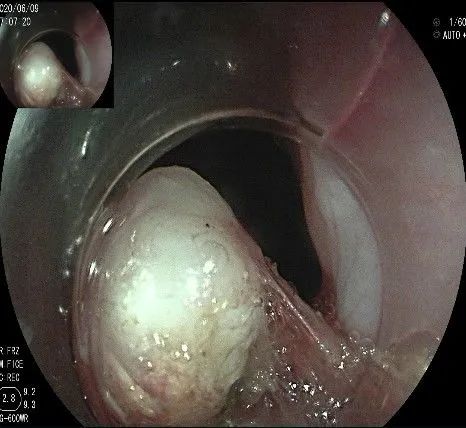

剥离接近完成,最后连接的薄层组织。

瘤子完整切除,随透明帽吸出的时候脱落到左侧会厌部,当时我们团队的麻醉、护理等人员都捏了一把汗,因为是静脉全麻没有插管,离声门太近了,一不小心进入气道会形成气管异物,造成严重后果!迅速换用鳄齿钳钳夹牢固,顺利取出!

完整的瘤体,呈不规则形状,长约2.0cm,宽度约0.8cm,有一定厚度,触之韧,像一颗白色的肾,表面有血管网。尽快浸泡送检。